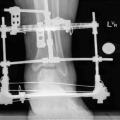

If extension stiffness occurs during femur lengthening, especially during formation of a regenerate in the distal third of the segment and the closed manipulation failed, external fixation can be used. For this purpose, a transosseous Ilizarov module is mounted on the lower leg (Fig. 11.1a) or the module is based on two half-pins and a wire (Fig. 11.1b). The module is connected by a hinge subsystem to the basic support. This approach should be used if extension stiffness forms during treatment of femoral fractures, specially open injuries to the distal third of the segment. This approach ensures that the emergence of rough cicatricial unions of tendons and muscles with the bone in the place of the fracture is avoided (Trick 11.1).

Fig. 11.1

(a–c) Schemes for an Ilizarov device (a) and a combined (hybrid) device (b) for reduction of the lower leg. The external supports of the module fixed to the femur are located parallel to the axis of the femoral condyles. Distraction starts on the 3rd to the 5th day at a rate of 0.25 mm six to eight times a day. The distraction rate is decreased if pain or signs of hyperextension of the great vessels and nerves occur. In lateral (external, internal) dislocations and subluxations, the distraction first must be uniform on all three hinges. After radiographic confirmation of the presence of the necessary diastasis for unhindered movement of the lower leg in the horizontal plane, the subsystem connecting the modules is remounted. The remounting depends on the type of dislocation: anterior, posterior, medial, or lateral. After reduction of the dislocation, the knee joint is fixed in the mid-physiological position for 2–3 weeks. After that the device can be used to develop movements in the knee joint (c)